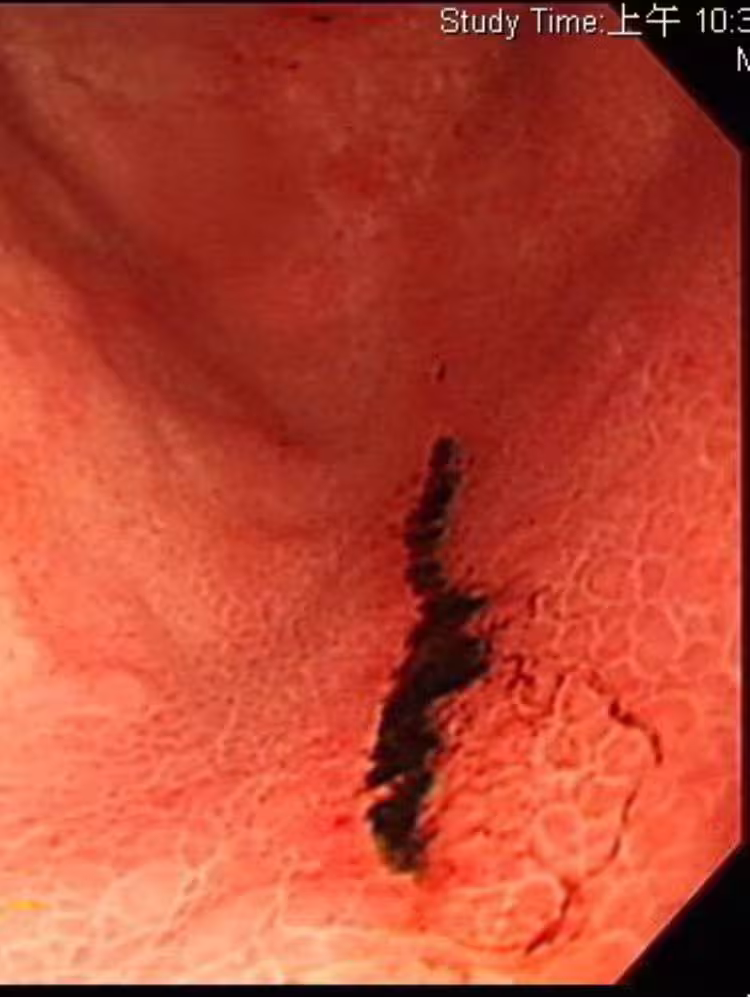

肚子爆痛拉黑糞!他生活超養身「胃竟冒5潰瘍」全爛光!醫一問才知「每天都喝1飲料」驚呼:酸度爆表

經過醫師的精密檢查,發現這名40多歲男子的胃竟有多達5處的潰爛傷口,某些嚴重的部位甚至有出血情況,可見病情嚴重。 但離奇的是,平時他並沒有不良習慣,用餐也相對清淡、規律,更沒有喝咖啡、茶、果汁等飲品,甚至連零食都沒有吃,照理來說並不會出現那麼可怕的潰瘍傷口。